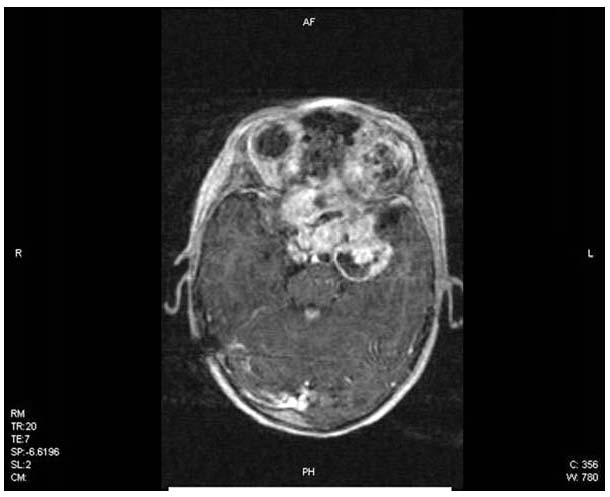

Většina tumorů této lokalizace jsou pilocytické a difúzní

astrocytomy (obrázek 1 a 2). Nádory chiasmaticko-hypothalamické

oblasti mají zvýšené riziko diseminace i přes ´low-grade´

histologii (obrázek 3). Suverénní diagnostickou metodou je MRI, byl

Obrázek 3 – Rozsáhlý pilocytární astrocytom

optické dráhy, MR, vyšetření s k.l.